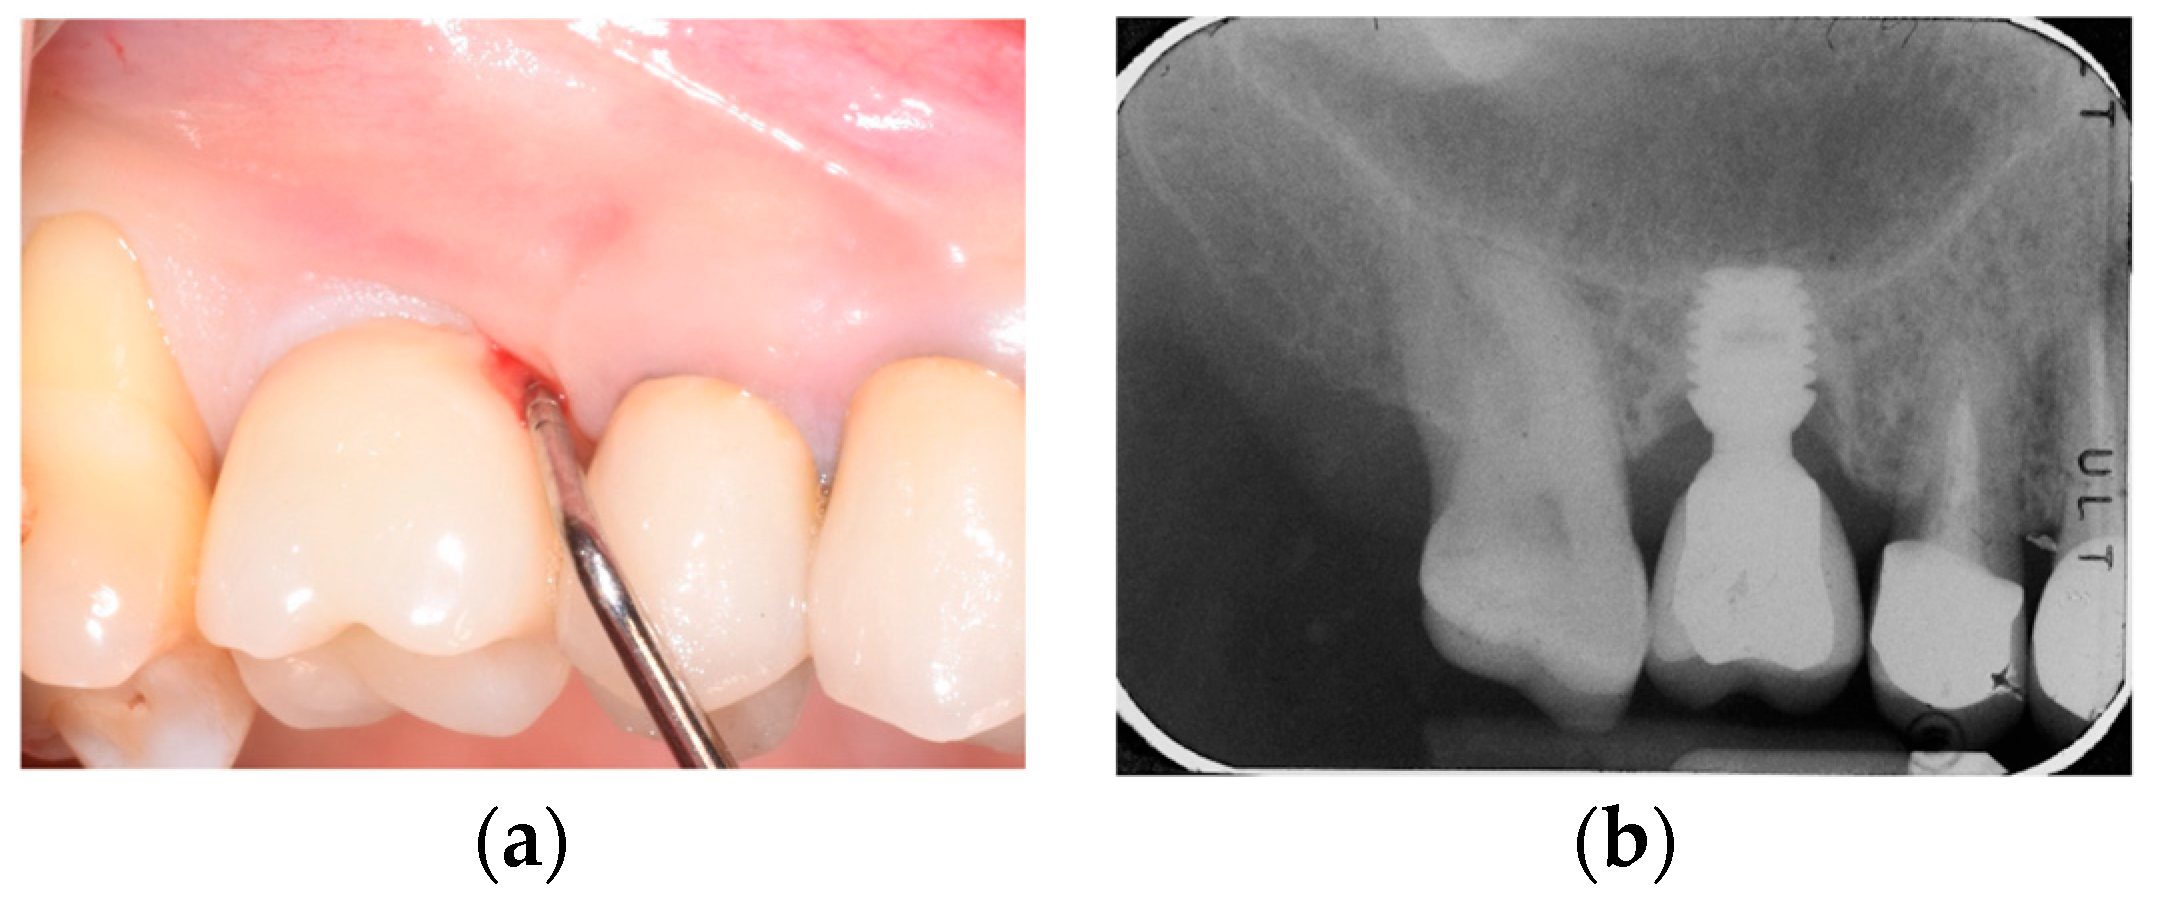

2.2. Surgical Protocol